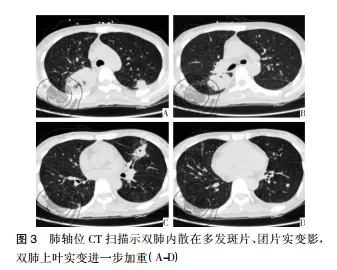

病例资料患者女性,42岁,因“咽痛、牙龈肿痛、发热20余天”于2017年5月13日入院。既往否认肝炎、结核及手术史。查体: 体温 37.8 ℃,贫血貌,齿龈增生,头颈部浅表淋巴结可触及肿大。咽部略充血、红肿,双肺、心脏、腹部查体未见异常。血常规: WBC 4.5×109 /L,RBC 2.23× 109 /L,PLT 67× 109/L,Hb 78 g /L,中性粒细胞绝对值( NE#) 0.22×109 /L。入院后给予抗炎治疗,体温降至正常。经骨髓活检确诊为急性髓系白血病 AML-M5( 中危组) ,于2017 年5月16日起行( 去甲氧柔红霉素+阿糖胞苷) 方案化疗。化疗间歇第14天,骨髓象未缓解,患者出现间断发热,炎性指标超敏C反应蛋白升高,肺CT提示肺内感染、脾脏未见异常,见图 1。故采用伏立康唑加亚胺培南联合抗炎治疗。化疗间歇第21天,骨髓象部分缓解。2017 年 6 月 26 日起给予方案强化巩固治疗。第二化疗间歇第8天,患者出现发热,体温达 39 ℃,伴寒战、大汗,超敏C反应蛋白 47.20 mg /L,降钙素原 19.81 ng /ml,痰培养见肺炎克雷伯菌肺炎亚种,复查肺CT提示肺内感染加重。先后给予美洛培南、阿米卡星、伏立康唑、替考拉宁、泊沙康唑、万古霉素及左氧氟沙星抗感染治疗。第二化疗间歇第16天,患者出现左季肋部疼痛,腹部彩超未见明确异常。腹部CT显示脾实质不均匀低密度伴周围渗出,见图 2。给予抗炎及对症治疗,患者仍间断发热及左季肋部疼痛。第二化疗间歇第 57 天,患者左侧肋下局部软组织隆起,皮肤变红及皮温升高,1周后左侧肋下包块破溃,流黄白色脓液及偶伴臭味,脓汁真菌涂片查到真菌孢子。胸腹部 CT提示肺内真菌感染,见图 3; 脾实质内液气混杂密度影,蔓延至左侧胸腹壁,累及结肠脾曲、左肾实质,伴左侧第10-11肋骨骨质破坏,见图4。遂于2017年9月18日全麻下行剖腹探查术,术中见腹腔大量脓液及粪便,胃、脾表面被覆脓苔,脾脏体积小,脾脏结肠瘘。遂行脾切除术、左侧腹壁窦道切除、结肠脾曲部分切除、肠吻合术及回肠造瘘术,并行胃部分切除术。术后病理示脾坏死、结肠穿孔,坏死周围及穿孔区周围、胃壁浆膜及肌层见大量急慢性炎细胞浸润、脓肿形成、肉芽组织及纤维增生,伴多核巨细胞反应及坏死样物,见图 5。患者病程中白细胞计数及超敏C反应蛋白变化过程如图 6 所示。术后患者恢复较好,进食、排气排便正常,于9月27日顺利出院。